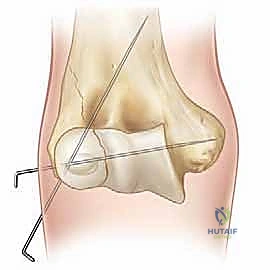

Once anatomical reduction is visually confirmed, it is provisionally held in place. This can be done with a smooth K-wire used as a "joystick," or by having an assistant maintain pressure with a dental pick. The reduction is then rigorously verified under multi-planar fluoroscopy. The surgeon must scrutinize the AP, lateral, and oblique views to ensure there is no residual step-off, gap, or rotational malalignment.

Definitive Internal Fixation Constructs

Definitive fixation is standardly achieved utilizing two or three smooth Kirschner wires (K-wires), typically 1.6 mm or 2.0 mm in diameter, depending on the size of the child. The trajectory of these wires is critical for biomechanical stability. The first wire is usually driven from the lateral epicondyle, directing it proximally and medially, aiming to engage the intact medial cortex of the distal humeral metaphysis.

The second wire should be placed divergently from the first to maximize rotational stability. A common and highly effective configuration is to place the second wire slightly more anteriorly and direct it more transversely across the distal humerus, aiming for the medial column above the olecranon fossa. It is imperative to avoid penetrating the olecranon fossa with the K-wires, as this will mechanically block elbow extension.

In older children or adolescents with a large metaphyseal fragment, a cannulated screw (typically 3.5 mm or 4.0 mm) can be utilized for compression across the metaphyseal fracture line, supplemented by a K-wire for rotational control. However, screws must never cross the physis. Once fixation is secure, the K-wires are bent, cut, and typically left protruding through the skin to facilitate easy removal in the clinic, although some surgeons prefer to bury them beneath the skin to reduce infection risk. The wound is then copiously irrigated and closed in layers.